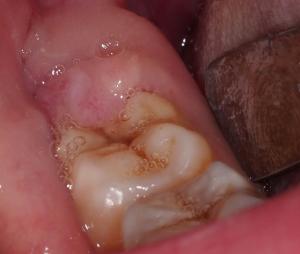

EE presented with recurrent pain and swelling on the lower right side, where the wisdom tooth had been partially erupted for the past 7 years. This was occurring because there was a flap of gum at the back of the tooth which kept getting plaque and bacteria growing underneath:

EE expected to need to have the wisdom teeth removed. After detailed assessment was made, it was found that the wisdom tooth was actually coming up properly aligned and didn’t need removal.

Instead, it was possible to simply recontour the bone and gum around the back of the tooth to allow the wisdom tooth to be exposed properly – a procedure that is much less traumatic that the removal of the tooth, which normally results in a swollen and bruised face for at least a week.